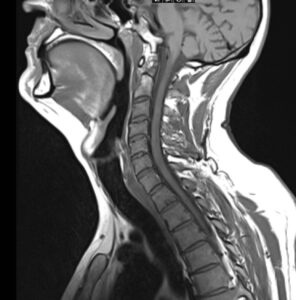

In der MRT werden mit einem starken Magnetfeld durch die elektromagnetische Anregung und Relaxation von Wasserprotonen im Gewebe Bilder erzeugt. So kann das Innere des menschlichen Körpers sehr detailliert und – im Gegensatz zur CT – ganz ohne Röntgenstrahlung abgebildet werden.

Dafür wird unser Körper Schicht für Schicht gescannt, sodass zunächst zahlreiche zweidimensionale Schnittbilder in hoher Auflösung angefertigt werden. Diese können anschließend am Computer übereinandergelegt werden, wodurch ein dreidimensionales Bild entsteht.

Dabei besticht die MRT durch einen hohen Weichteilkontrast – insbesondere Bindegewebe inklusive Nerven und Gefäßen, Muskeln und Fettgewebe lassen sich optimal beurteilen. So lassen sich sowohl entzündliche Prozesse als auch tumoröse Veränderungen der Halsweichteile, der Speicheldrüsen, des Rachens und des Kehlkopfes hervorragend darstellen und sicher befunden.

Auch die Halswirbelsäule und Teile des Rückenmarks sind auf einer MRT des Halses in der Regel dargestellt, sodass auch hier mögliche Pathologien diagnostiziert oder ausgeschlossen werden können.

Darüber hinaus können auch Flüssigkeitseinlagerungen in den Stimmbändern sowie Auffälligkeiten der Halsmuskulatur, die beispielsweise Schluckbeschwerden oder Fehlhaltungen im Sinne eines Schiefhalses hervorrufen können, und mögliche Bandscheibenvorfälle im Bereich der Halswirbelsäule mittels MRT festgestellt werden.